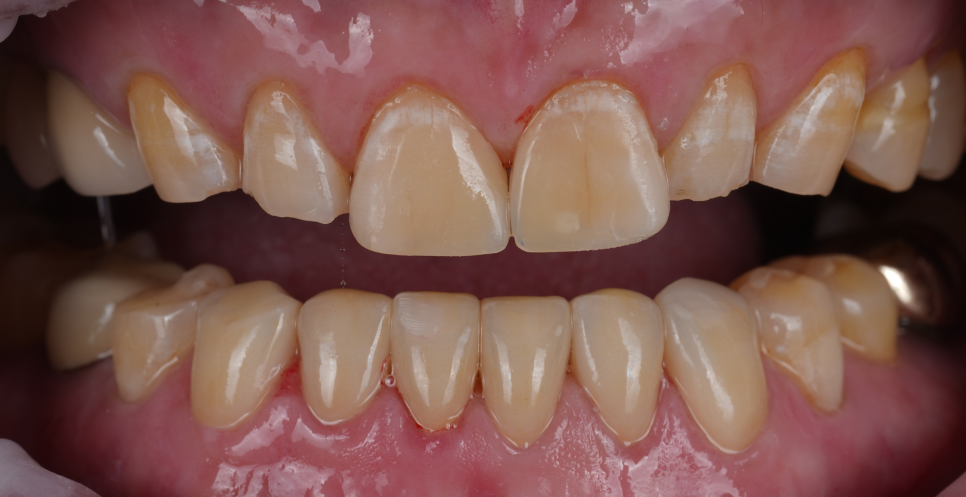

깊게 물리는 교합으로 이미 많이 닳아버린 앞니들

촬영일 : 251013

아래 앞니는 치아 윗부분(절단면)이 많이 닳아서 길이가 눈에 띄게 짧아져 있었고, 닳아 없어지면서 사이사이에 빈 공간이 보였어요.

뿐만 아니라, 치아 겉 부분(법랑질)이 모두 닳아 신경과 가까운 상아질이 모두 노출되어 있었는데요.

이렇게 상아질이 노출되어 있으면 시린 증상이 나타나며, 장기간 지속될 경우 신경까지 괴사될 수 있어 치료가 시급한 상황이었습니다.

또, 아랫니가 많이 닳아있어 깊게 무는 형태인 'Deep bite(딥바이트)' 라고 부르는 과개교합 상태였죠.

오랜 시간 서로 부딪히며 위아래가 서로를 갈아버린 흔적이죠.